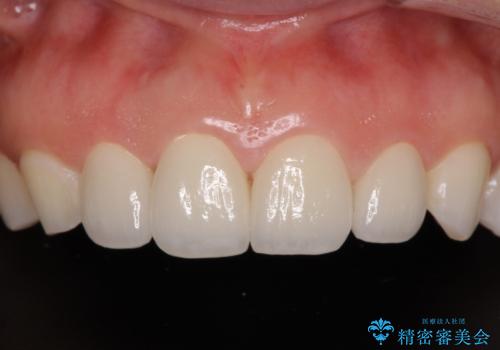

- 大きすぎる上顎前歯と、隙間の空いた下顎歯列を気にして来院された患者様です。

上顎前歯にはセラミッククラウンが装着されており、顔や他の歯と比較して幅の大きい状態でした。

下顎前歯は空隙歯列弓であったので、アンカースクリューとワイヤー装置を用いてスペースを閉じていくこととし、上顎前歯は矯正治療用の仮歯に置き換えた上で、仮歯の大きさを削って小さくしながら、上下前歯部の部分矯正を行うこととしました。

矯正治療後は、仮歯とした上顎前歯をオールセラミッククラウンにて補綴治療を行うこととしました。

日本と海外を拠点に仕事をされていらっしゃるため、数ヶ月治療があいてしまうことがあり、期間はかかりましたが、2年間で望み通りの前歯に仕上げることができました。